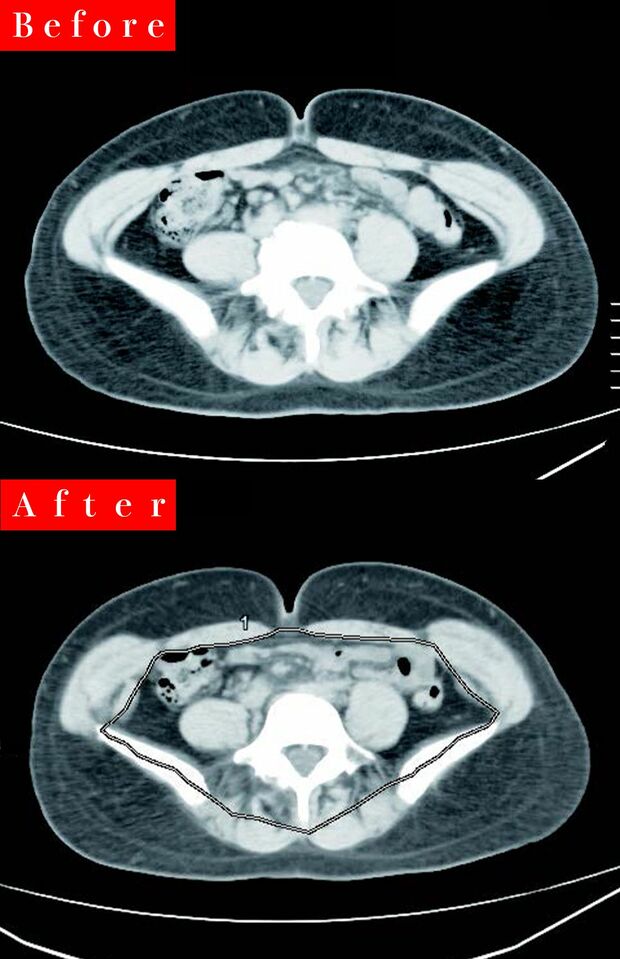

ライフ 2024/3/17 医師が実践して体重マイナス6kg減に成功!運動しないで内臓脂肪が勝手に落ちる楽チンダイエット!「MCTオイル」で痩せ体質・満腹フードで糖質オフ・ヘルシー間食 健康ダイエット成功医師食事レシピ血糖値栄養市川海老蔵 印刷 【写真】無理な食事制限なし!40代医師のマイナス6kgビフォー&アフター 齋藤真理子先生●形成外科専門医、医学博士。分子栄養学認定医。現在は山本メディカルセンター院長。テレビをはじめとするメディアでも活躍中。近著に『勝手に内臓脂肪が落ちていく食事術』(アスコム刊)。 内臓脂肪を減らしてマイナス6kg! ※写真はイメージです ※写真はイメージです ※写真はイメージです ※写真はイメージです 広告を見ると、続きの写真を見ることが可能になります 続きの写真を見る ページをリロードする 記事詳細を見る facebook いいね X ポスト LINE はてなブックマークに追加 健康の記事一覧を見る タレコミを投稿する 今日の運勢を無料で見る コピーしました